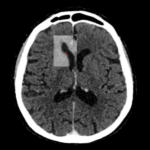

Existen casos donde podremos observar un aumento del espacio subaracnoideo lo cual no debe informarse como patológico o como atrofia yo que el mismo puede simplemente deberse a un hallazgo de naturaleza constitucional.

En relación con la atrofia cortical que es propia de los pacientes añosos, esta no debe confundirse con higromas o hematomas subdurales crónicos.

Fig. 7.